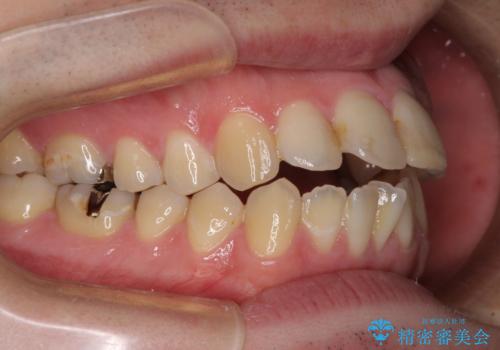

- 口がうまく閉じられないとのことで来院された患者様です。

上下唇をしっかり合わせようとすると、顎先が前方に突出してしまうほど口が閉じにくい状態でした。

口元の突出感を改善するために上下左右の第一小臼歯4本を抜歯し、ワイヤー装置にて矯正治療を行うこととしました。

また、上下前歯は舌の突出癖による開咬となっていたため、舌のトレーニングを徹底するよう指示しました。